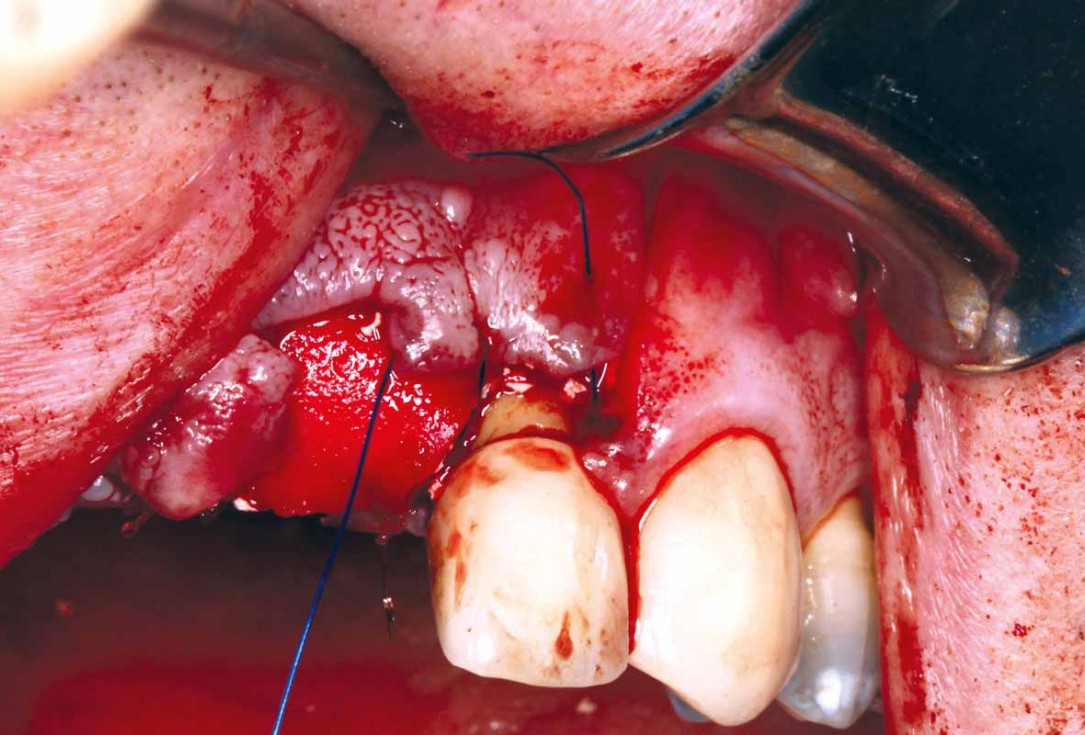

2/27 - Bone defect after raising the flap

GBR and soft tissue augmentation with cerabone® and mucoderm® - H. Maghaireh & V. Ivancheva

3/27 - Root extraction #21